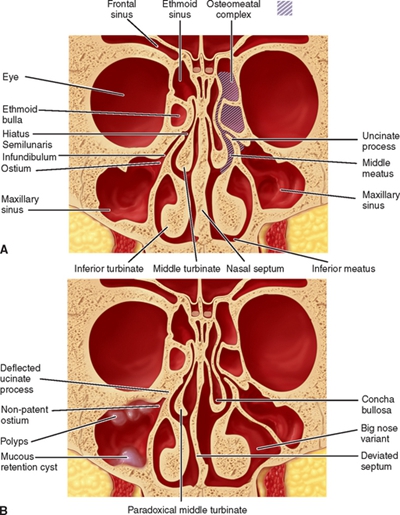

鼻中隔彎曲手術圖解 (44)

鼻中隔彎曲手術圖解 (45)

鼻中隔彎曲手術圖解 (46)

鼻中隔彎曲手術圖解 (47)

鼻中隔彎曲手術圖解 (48)